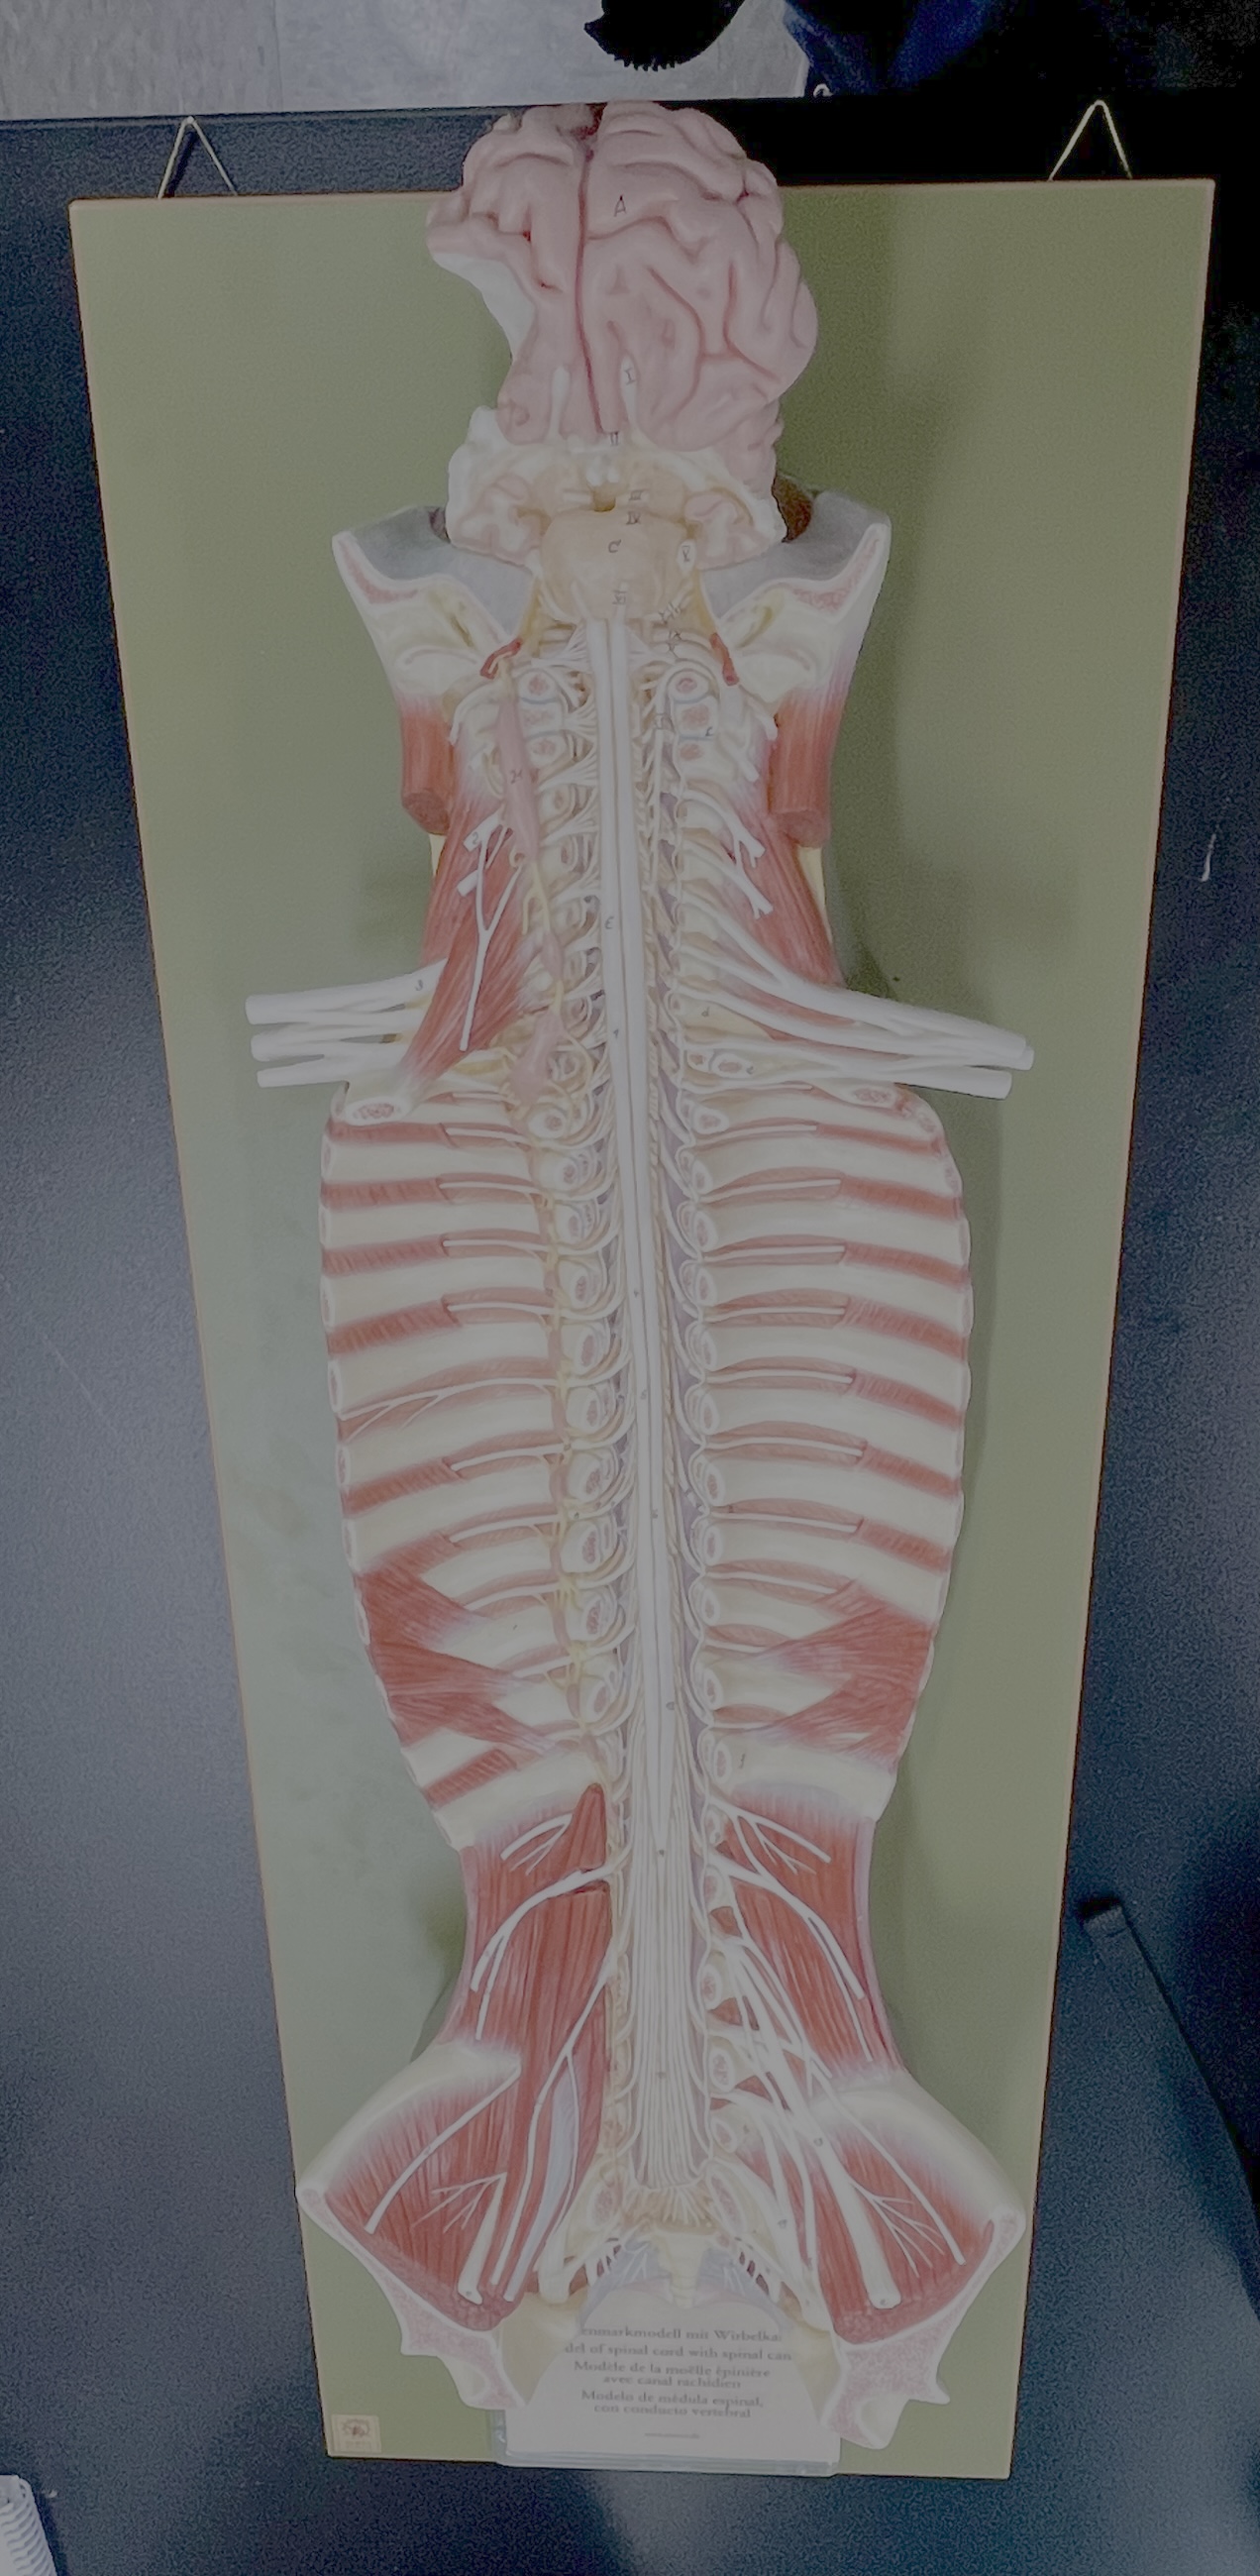

What type of spinal nerve is this? How many pairs?

cervical (8 pairs)

What type of spinal nerve is this? How many pairs?

thoracic (12 pairs)

What type of spinal nerve is this? How many pairs?

lumbar (5 pairs)

What type of spinal nerve is this? How many pairs?

sacral (5 pairs)

What type of spinal nerve is this? How many pairs? (not pictured)

coccygeal (1 pair)

cervical enlargement

cervical enlargement

thoracic segment

lumbar enlargement

lumbar enlargement

conus medullaris

conus medullaris

filum terminale

cauda equina

sympathetic chain ganglia

cervical plexus – phrenic nerve

cervical plexus – phrenic nerve

brachial plexus – ulnar nerve

brachial plexus – median nerve

brachial plexus – radial nerve

lumbar plexus – femoral nerve

lumbar plexus - femoral nerve

sacral plexus – sciatic nerve

sacral plexus – sciatic nerve